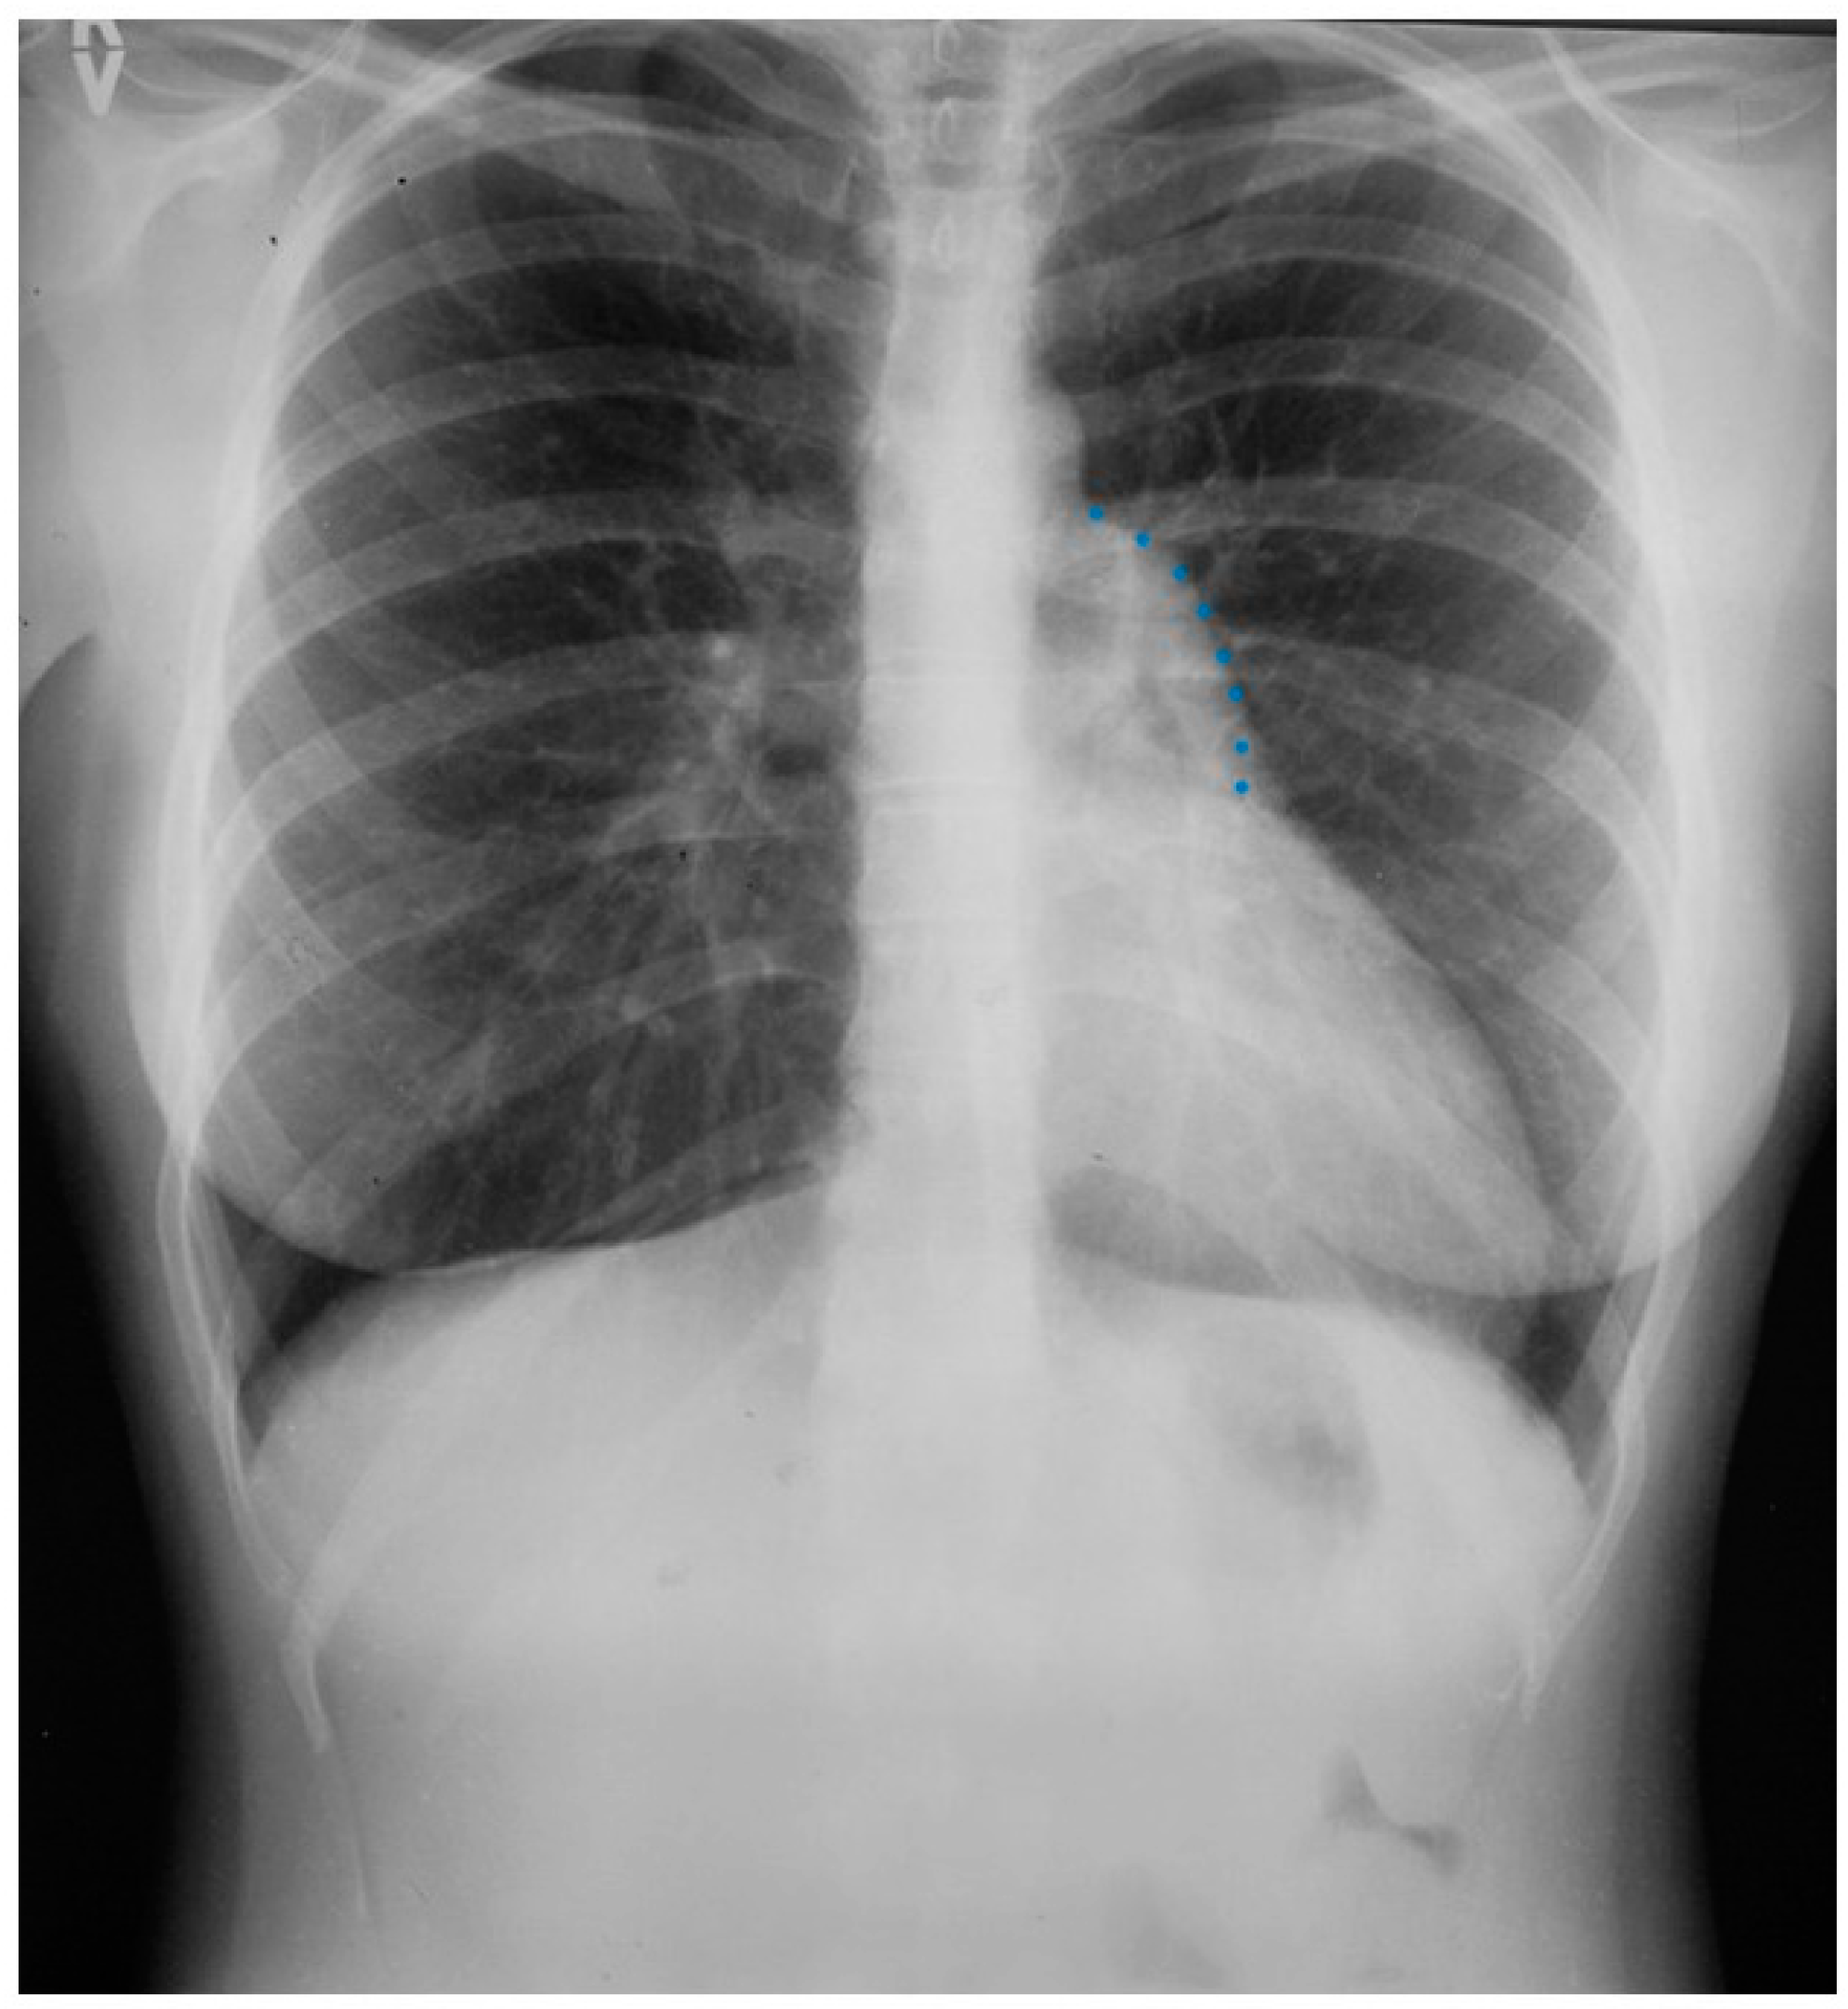

Figure 1.

Posteroanterior chest X-ray in congenital complete absence of the left portion of the parietal pericardium: A 30-year-old female was referred to a cardiologist because of an unusual chest X-ray done as part of an executive physical. She was asymptomatic and her vital signs and heart sounds were normal and there was no heart murmur or arrhythmia. The image is well centered, there is a good inspiration and the C-T ratio is <0.5. The heart is shifted into the left chest and the right heart border is obscured because it overlies the dorsal vertebral bodies. The pulmonary artery segment (outlined with blue dots) is enlarged but the pulmonary vascularity is normal, making left to right shunting unlikely. Echocardiography and Cardiac MRI confirmed she had CCALPPP. She was reassured. No treatment was necessary.